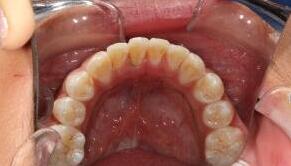

Celina,女,来自英国

现病史:上颌前牙轻度外翻

治疗方案:经过专业正畸医生检查后,制定陶瓷自锁托槽矫正方案。患者及家属同意矫正方案

优势:兼具了美观与舒适的优势,同时也具备了自锁托槽的高效快速排齐、轻力无痛的特点

五个月后牙齿排列整齐,患者表示满意!